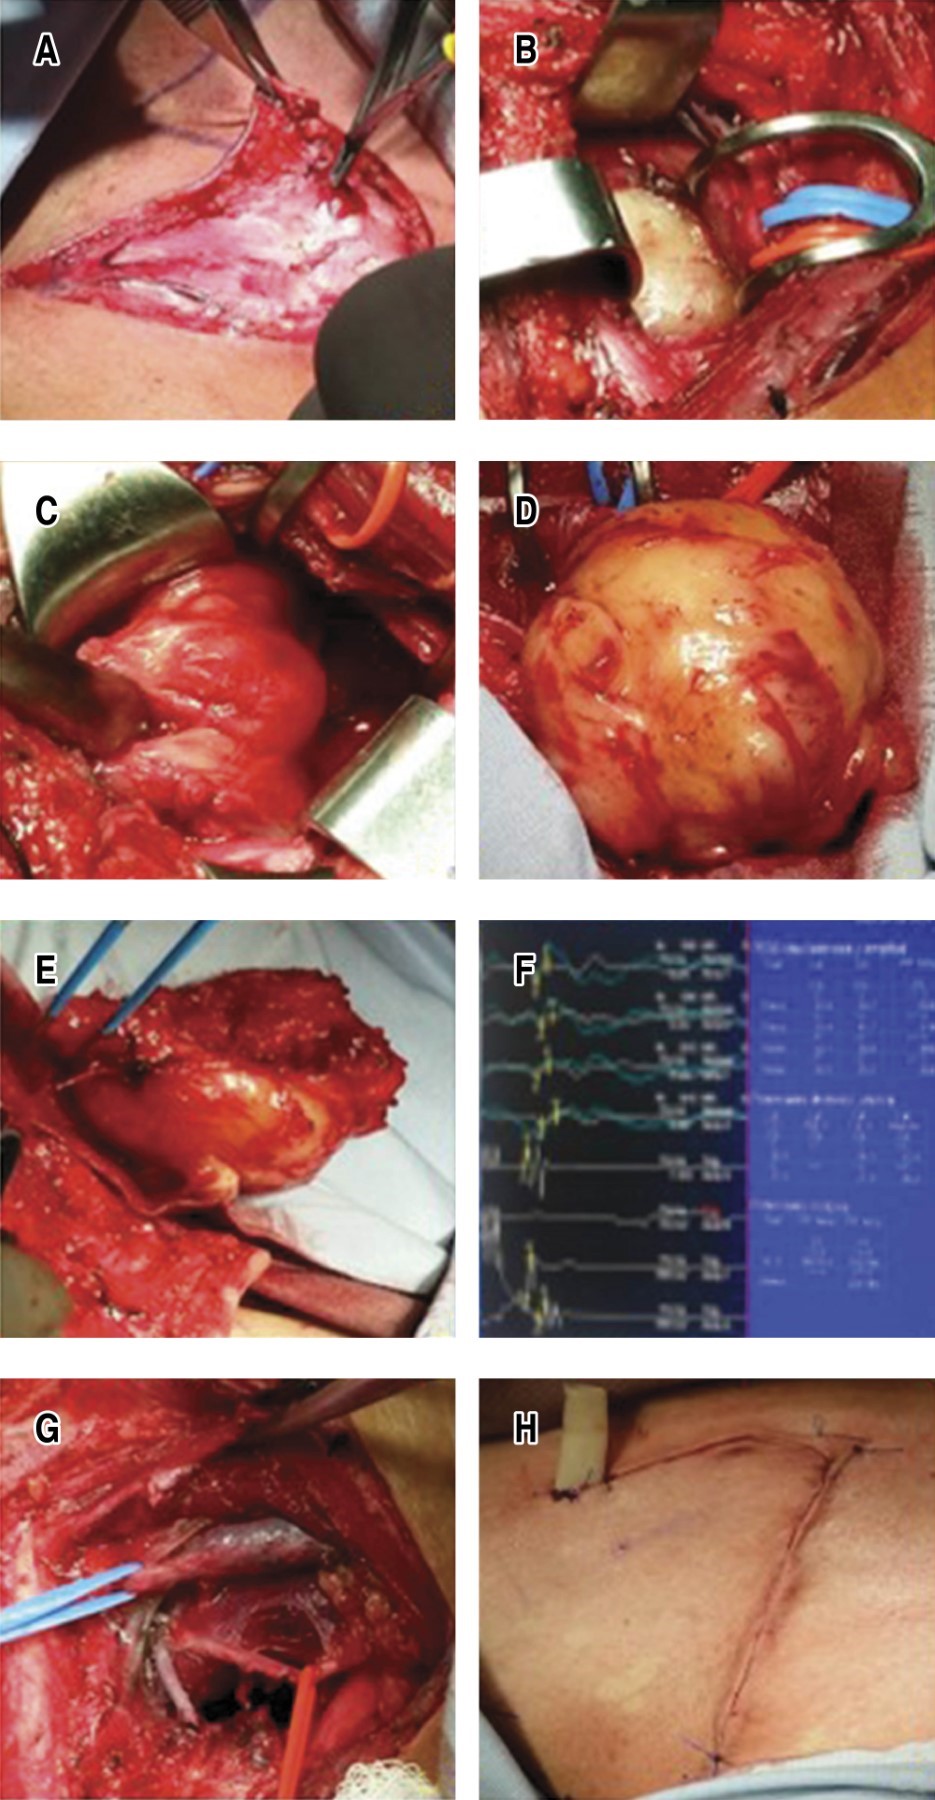

Se efectúa exéresis tumoral a través de abordaje cervicotorácico anterior con monitoreo neurofisiológico, encontrándose: masa esférica de 9 × 7 × 5 cm y encapsulada, resecada por enucleación central e intracapsular dependiente de raíces nerviosas C5, C6 y C7, extrapleural corroborado por un abordaje toracoscópico izquierdo, sin drenajes.

El reporte de patología es diagnóstico de schwannoma cervicotorácico. A las dos semanas posquirúrgicas se encuentra con recuperación de movilidad continuando con atrofia importante, sin embargo, presenta recuperación gradual de tono y fuerza muscular y movimiento en extremidad afectada a siete años de seguimiento con apoyo de rehabilitación (Figura 2A-H).

Las causas de déficit neurológico posoperatorias están relacionadas con compresión nerviosa preoperatoria, lesión mecánica o isquemia transoperatoria, reoperaciones asociadas a incompleta enucleación. Por lo anterior varios métodos de monitoreo neurológico perioperatorios han sido desarrollados, como la electromiografía espontánea (EMGe), los potenciales evocados somatosensoriales (PESS) y el potencial de acción nerviosa (PAN).8 Con la EMGe se realiza la estimulación nerviosa y se registra la actividad muscular para identificar o evitar el daño nervioso; con los PESS es útil para registro de lesiones del plexo braquial y evalúa si existe continuidad con el sistema nervioso central; con el PAN se estimula directamente el tronco nervioso proximal a la zona de lesión y obtiene un registro en la zona distal a la lesión, muestra utilidad en las lesiones nerviosas por continuidad y determina la necesidad de otros procedimientos de reconstrucción con injertos de nervio sural. Los pasos críticos en la resección quirúrgica del schwannoma del plexo braquial con la monitorización electrofisiológica de nuestro caso fueron: a) exposición del nervio proximal y distal al tumor por neurolisis; b) exposición capsular y electroestimulación del tumor para localizar y mapear la distribución funcional nerviosa; c) incisión longitudinal de la cápsula en el sentido de los nervios adyacentes sin actividad funcional registrable; d) enucleación y electroestimulación para evitar el daño de las fibras nerviosas funcionales; e) exposición final de los polos proximal y distal del tumor donde discurren los nervios y evaluación por PAN para determinar una potencial lesión por continuidad que requiera una reconstrucción con injerto sural; y f) monitorización posoperatoria de los déficit basales y funcionales para la rehabilitación y pronóstico futuros.

El schwannoma, en nuestro caso, facilitó la separación quirúrgica de las fibras nerviosas sanas y funcionales, no fue necesaria la neurorrafia o el injerto sural como se describe para los neurofibromas y malignidades primarias; el abordaje cervicotorácico anterior con una incisión en forma de L fue suficiente. Aunque debe considerarse el abordaje cervicotransesternal en contrapuerta, trap-door, ante masas invasivas de gran componente intratorácico y mediastinal.9,10